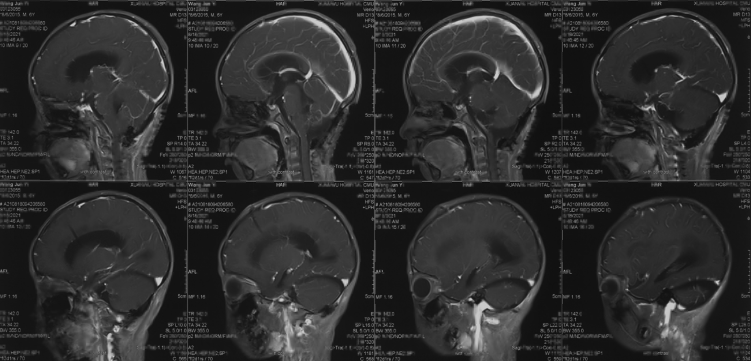

Pre-operative imaging

Preoperative enhanced MRI